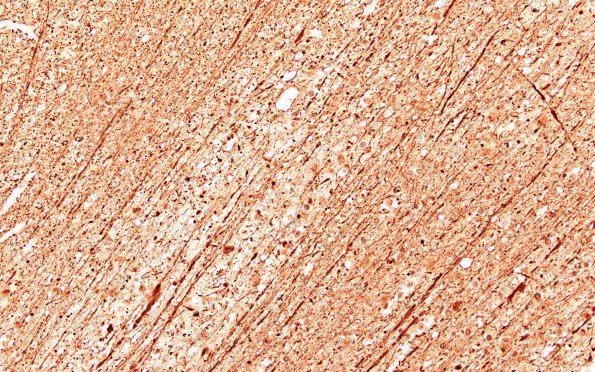

Several higher magnification images of the area between arrowheads in image 12D2 showing focal axon loss and swollen axonal spheroids at the margins of the embolic infarcts. Lucent empty vessels containing fat emboli are discernable close to individual infarcts. (NF IHC)